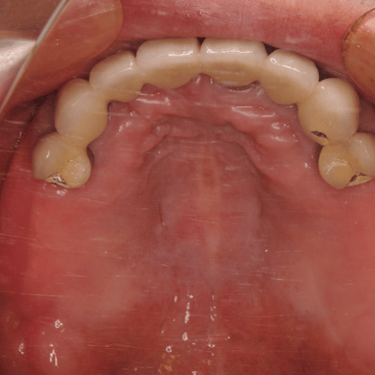

Edentulismo completo

El edentulismo completo es la ausencia total de dientes en una o ambas arcadas.

Los pacientes tienen dificultad para masticar, hablar y pueden sentirse incómodos con su apariencia.

El tratamiento puede incluir la colocación de una prótesis completa sobre implantes, proporcionando una solución fija y estable